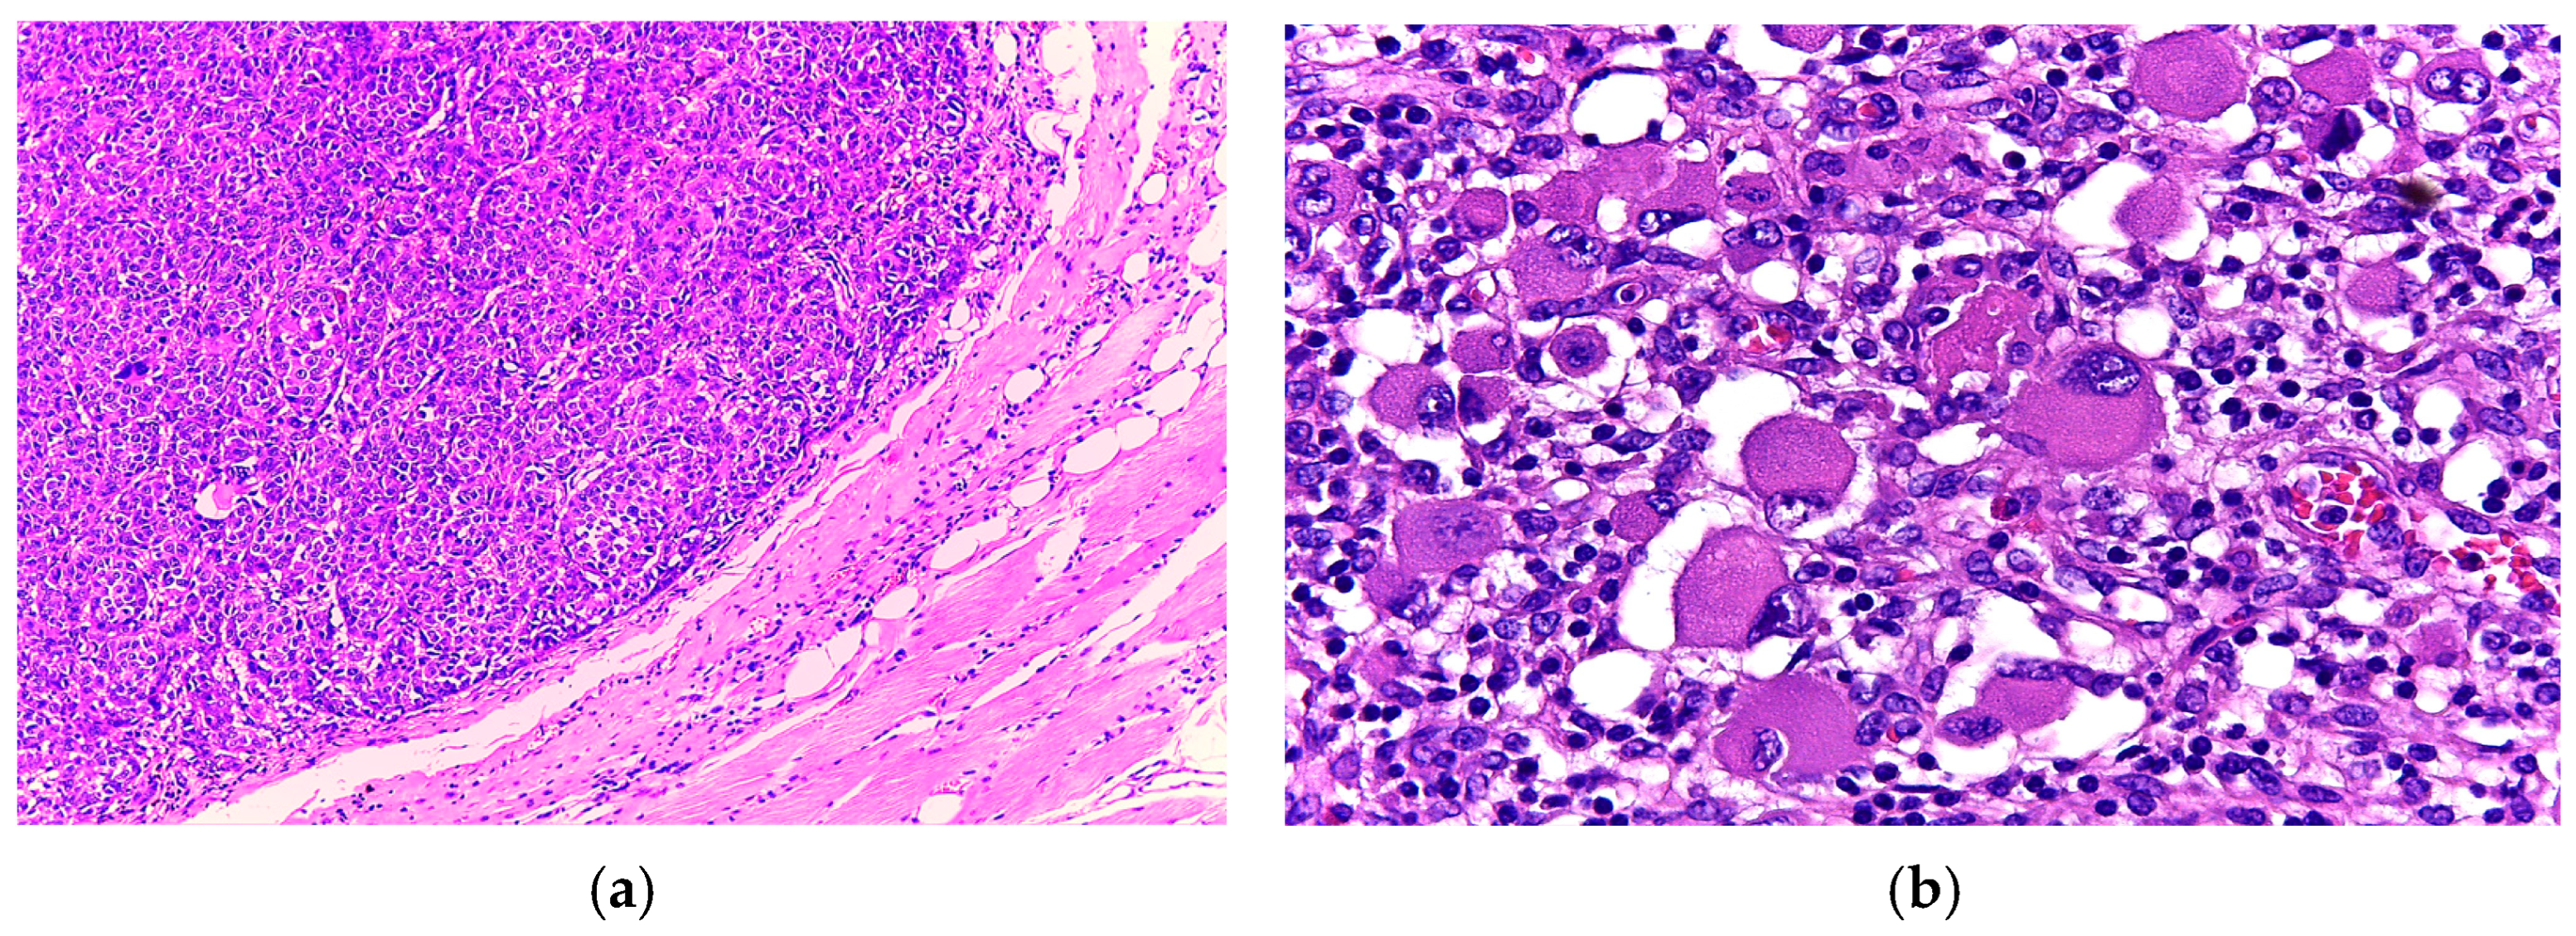

3.1. Case 1

3.2. Case 2